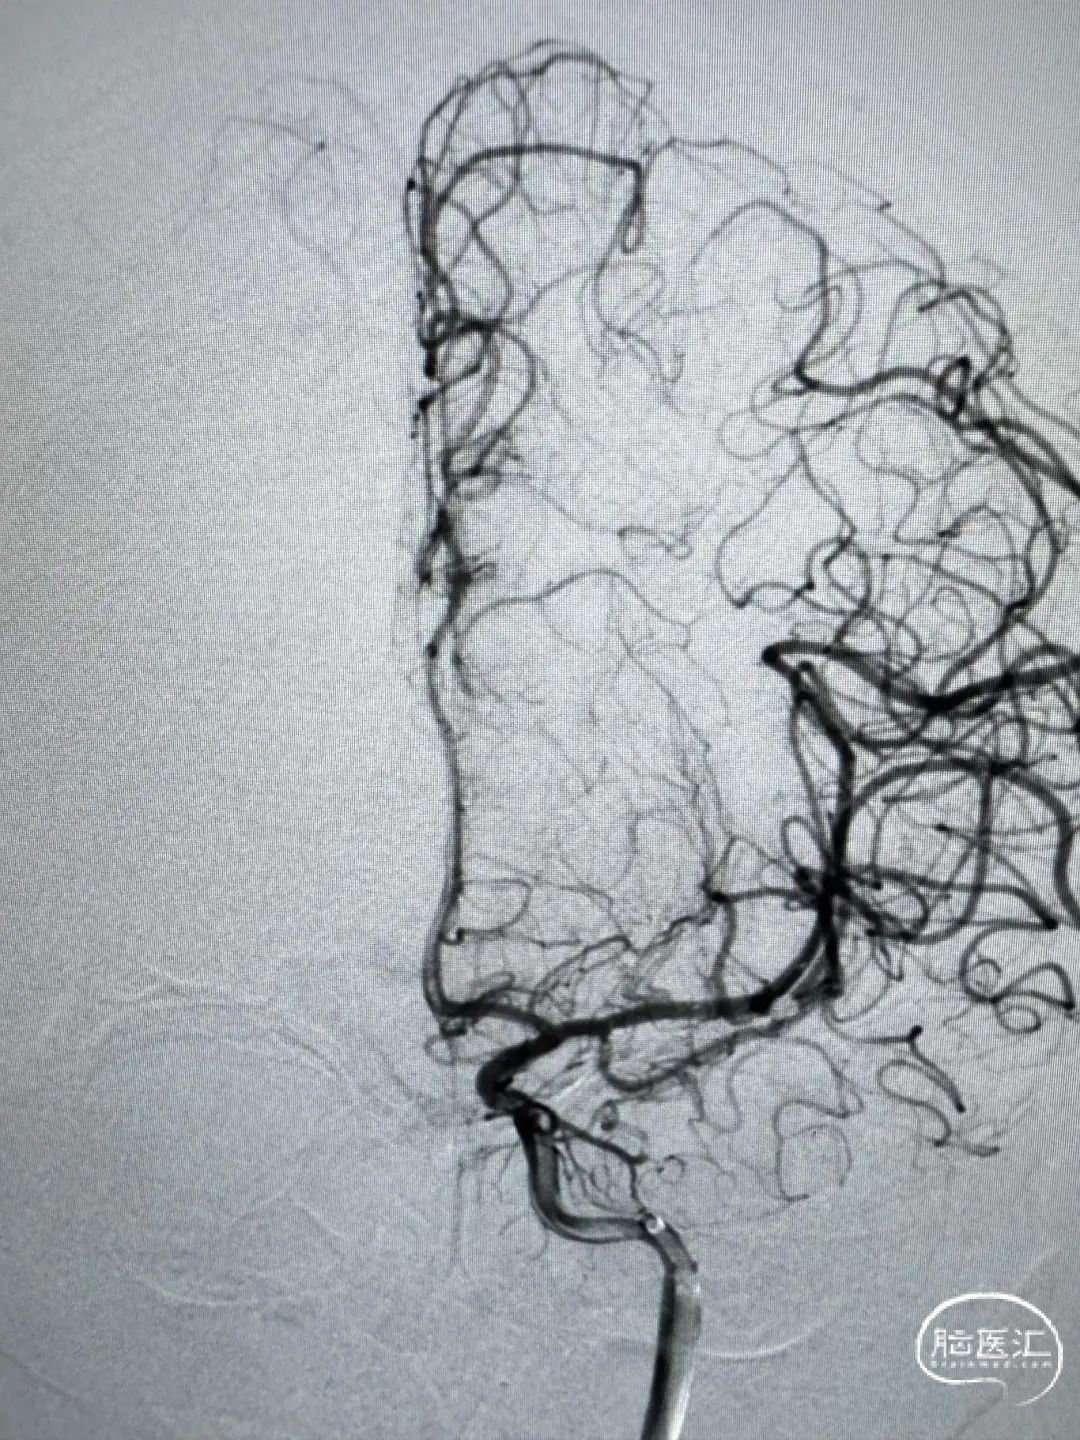

术后正侧位造影。

动脉瘤完美栓塞,一个支架,两根微导管,一根微导丝主导全程,填塞致密。

该例病案,“花开一支,各表一朵”,远端分叉处动脉瘤为责任动脉瘤,但颞干处动脉瘤呈“分叶状”。本次手术最大的难点在于颞干处动脉瘤的处理策略,分期处理的话,在血管痉挛期风险极大提高。如同期处理,从M1水平放支架,对瘤颈没有意义,且两个支架在M1中段可能会有交汇,对豆纹动脉的影响太大。如放在颞干,后期远端动脉瘤万一复发,那补救手术的难度太高。另颞干处为小型动脉瘤,分叶状,如超选两根微导管分区填塞,则空间不够。以上多方面考虑,本例动脉瘤对术者手感考虑比较大,最后颞干处动脉瘤弹簧圈裸栓成功,且经济成本明显下降。